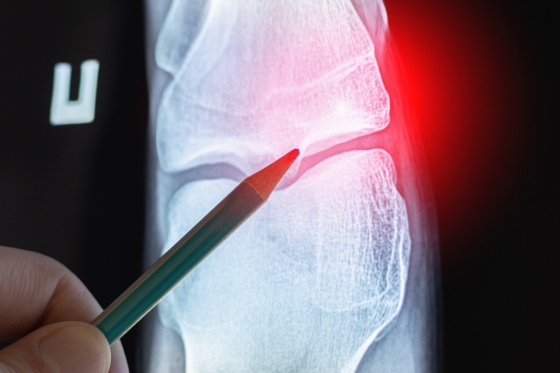

Osteom, metode de diagnostic

In functie de simptomele pe care le prezinta in cadrul anamnezei pacientului, medicul poate recomanda o serie de investigatii:

-

radiografie – pentru a avea o imagine generala asupra formatiunii osoase;

tomografie computerizata (CT) – se recomanda pentru evaluarea dimensiunii osteomului si pentru localizarea lui;